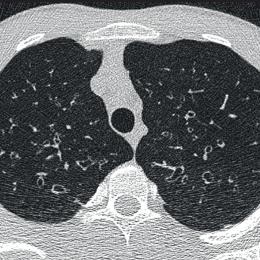

Lymphome de Hodgkin à localisation cutanée spécifique

Un homme de 25 ans consulte pour des symptômes respiratoires incluant une dyspnée, une orthopnée et une toux, accompagnés de l’apparition...